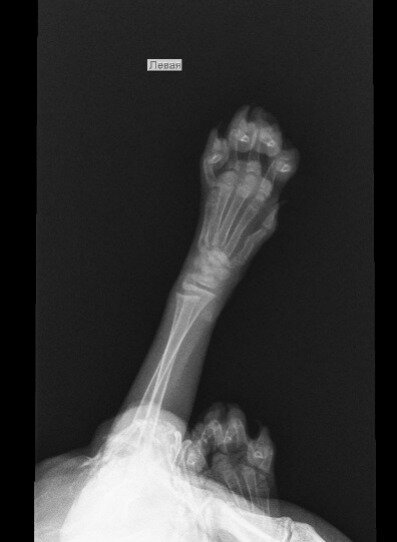

Доброго времени суток! Котенку 2 месяца, вчера поздно вечером случайно прижали дверью (не заметили как прошмыгнул), котенок сильно испугался и начал поджимать левую переднюю лапку. Наощупь серьезных повреждений не обнаружили, котенка успокоили и уложили спать. Утром попросил кушать, ковылял на трех лапках, продолжая держать левую переднюю на весу. Потом ближе к обеду разыгрался, бегал, прыгал и гонял игрушки как обычно. Решили все-таки на всякий случай показать ветеринару. Врач так же наощупь не нашёл ничего серьёзного, но сказал, что не нравится запястье, отправил на рентген. Сделали снимок в двух проекциях, косточки все целые, рентгенолог предположил, что возможен подвывих одной из маленьких косточек запястья, нужно показать кота и снимки хирургу-ортопеду. По возвращению домой котенок уснул. После сна опять начал прихрамывать, опираясь на больную лапку, и иногда поджимать её. Дело в том, что к хирургу мы попадём скорее всего не раньше конца недели. Может быть, кто-то сможет по рентген снимкам подсказать, есть ли подвывих? Нужно его вправлять? Заранее благодарю за ответы!